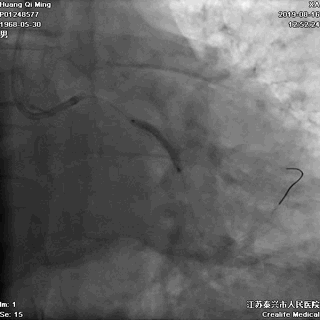

冠状动脉造影

右冠状动脉无严重狭窄

左主干前分叉处血管正常

LCX近中段病变,狭窄最重达90%

LAD中远段血管偏细,弥漫性病变,狭窄达90%

导丝通过病变

球囊扩张,PTCA